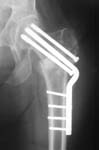

Does anyone on the list know of any references regarding the placement of cannulated hip screws above/below the lesser trochanter as it relates to the risk of subsequent subtroch fracture? i know placement should be above the lesser trochanter but i have been unable to find evidence to support this. thank you.

Reported 20% incidence of fracture if screws are placed too low, below the lesser trochanter, or  with un-filled drill holes there too. I have not looked at it in a long time but I believe the reference on this topic is: Karr, Clin Ortho Rel Res 1985.